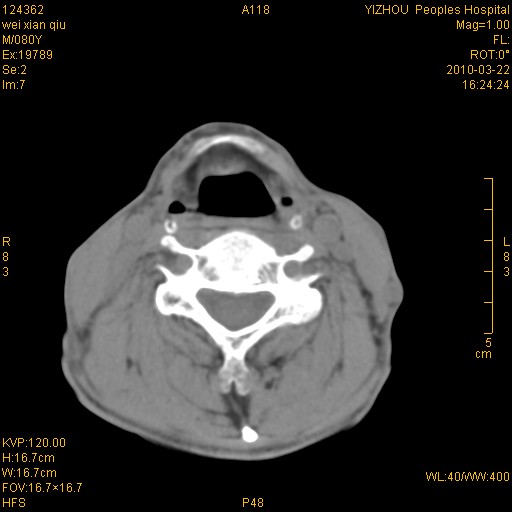

标题: CT25263:喉部占位?

男,80岁.声嘶三月余.

右侧喉癌可能性大,建议喉镜检查

喉前庭右侧壁明显增厚,并见向内突出的软组织密度新生物,表面光滑,其后方软组织层次尚清晰,多考虑:喉部乳头状瘤!建议喉镜并病检!

考虑喉癌;建议行喉镜检查(活检)进一步明确诊断。